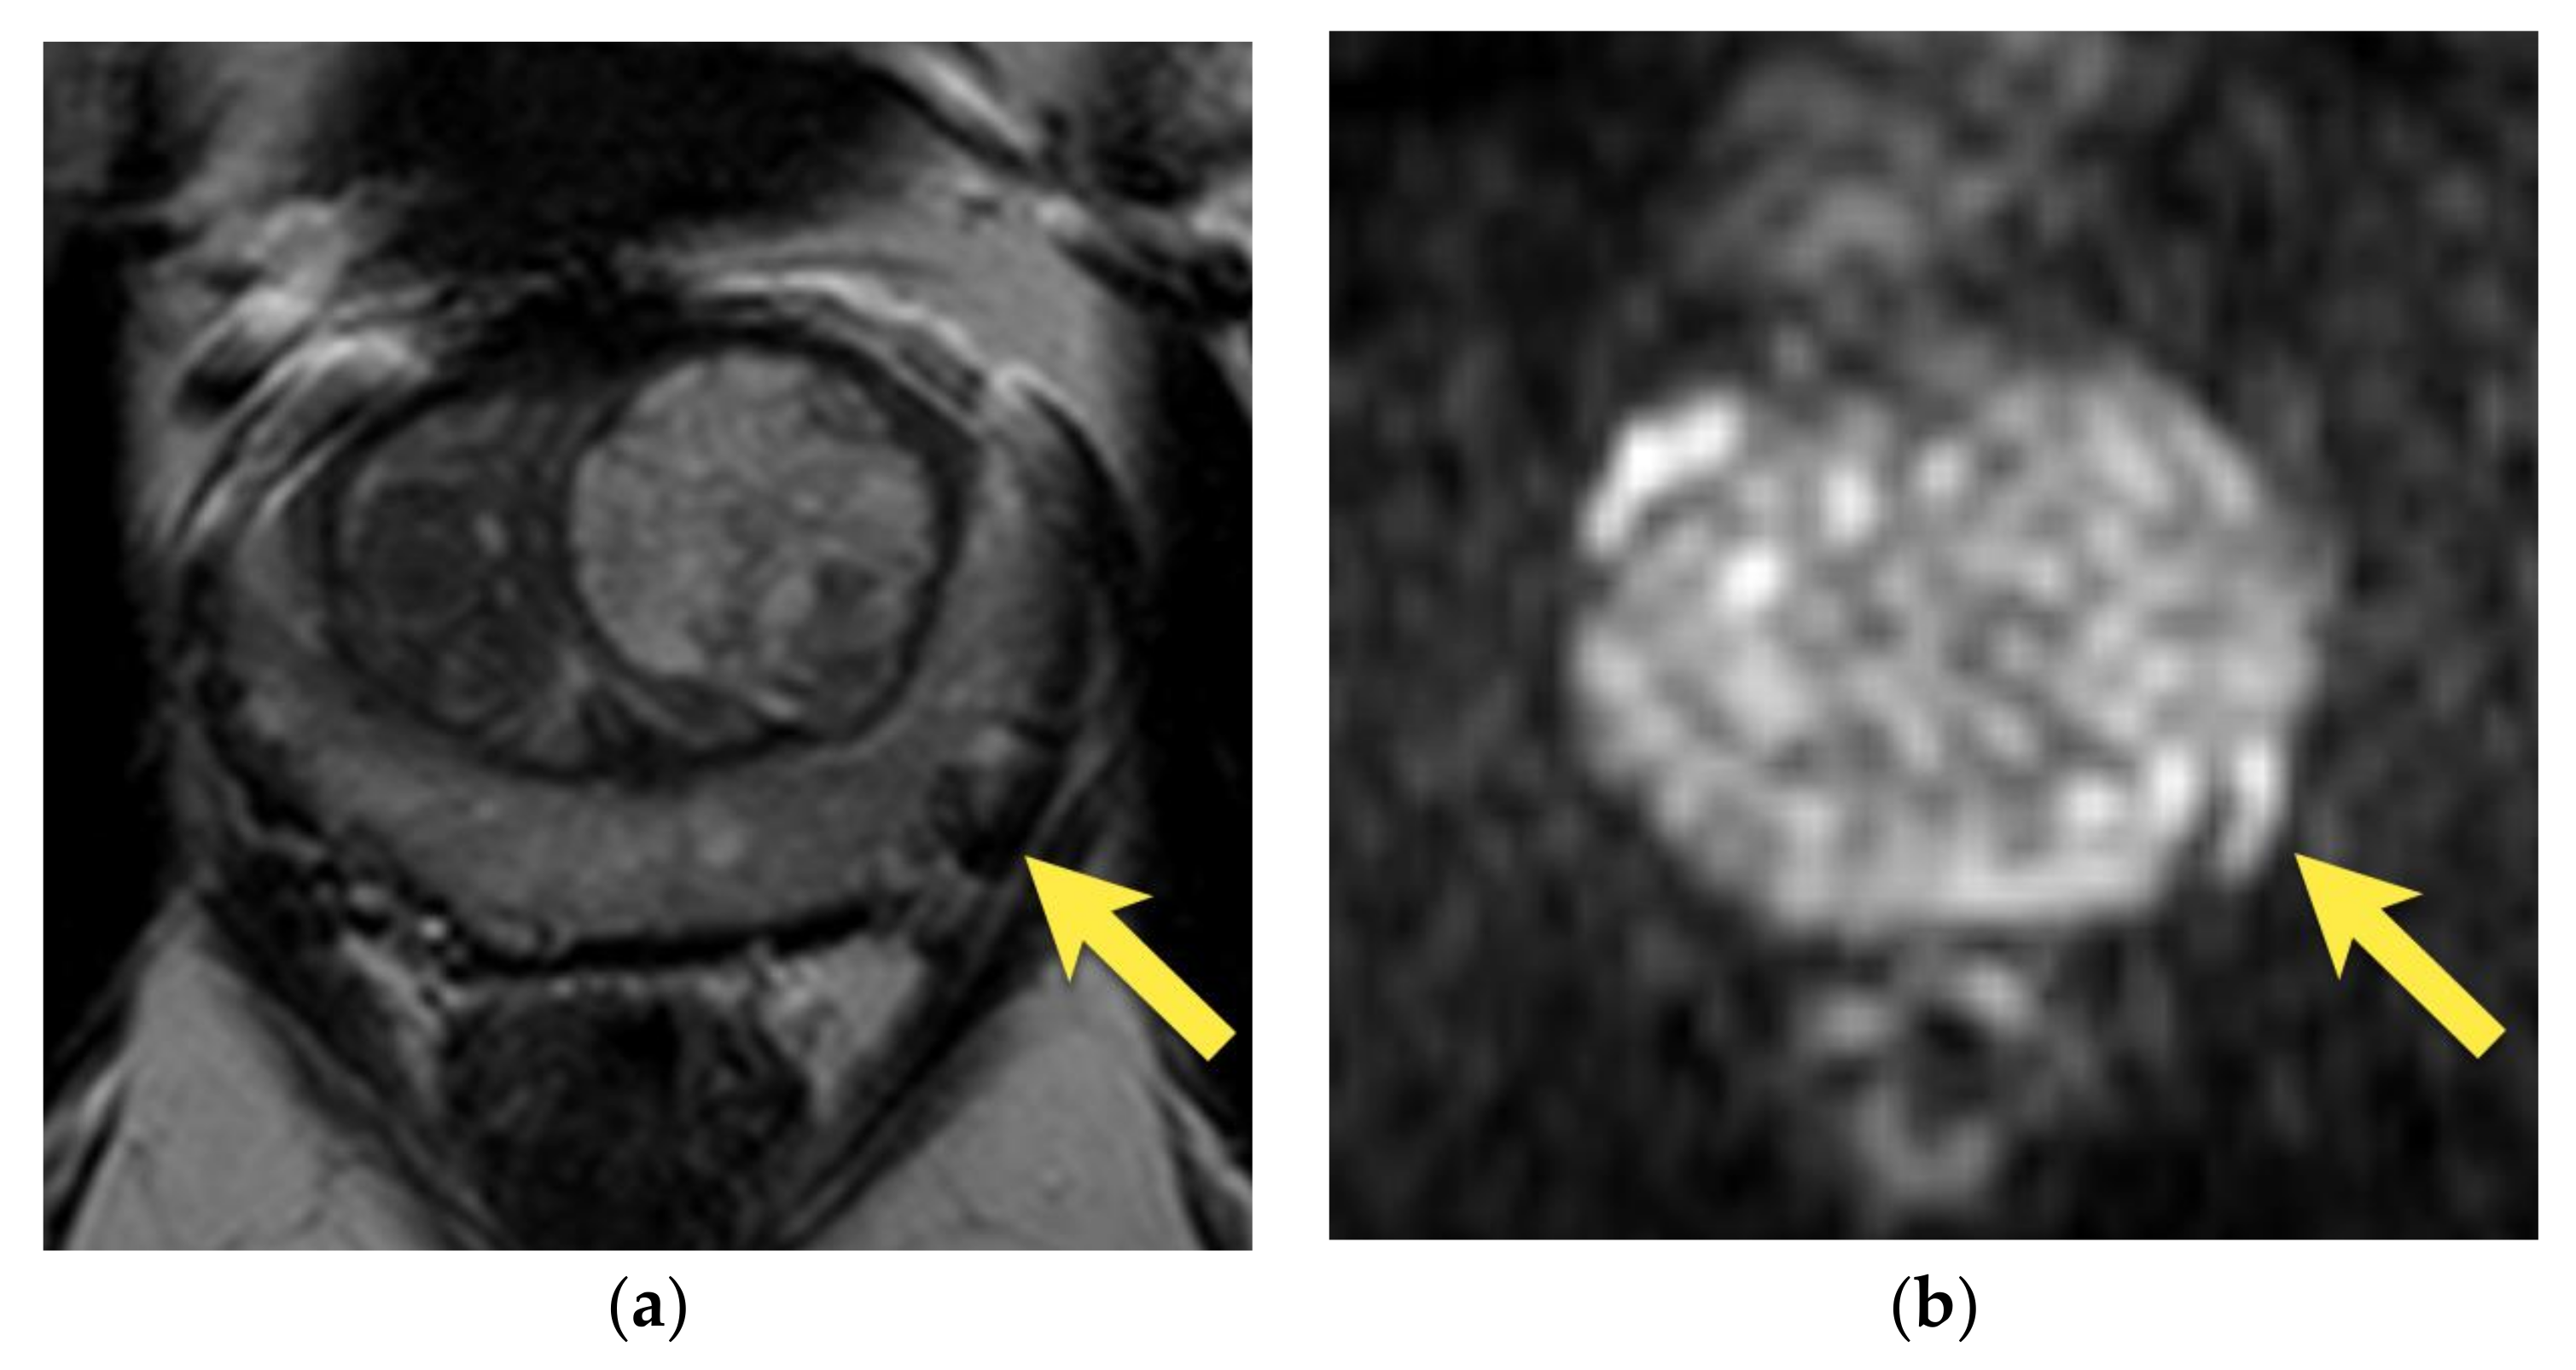

10. Prostatic Abscess